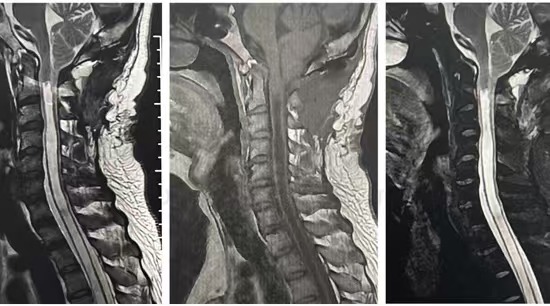

• 诊断:寰枢椎脱位、颅底凹陷、小脑下疝、脊髓空洞

• 影像:

• 2024.10.30,在宜宾二医院复查,螺钉脱离。类似喝醉的头晕,走路不稳,左手力量和灵活度下降,影像如下: